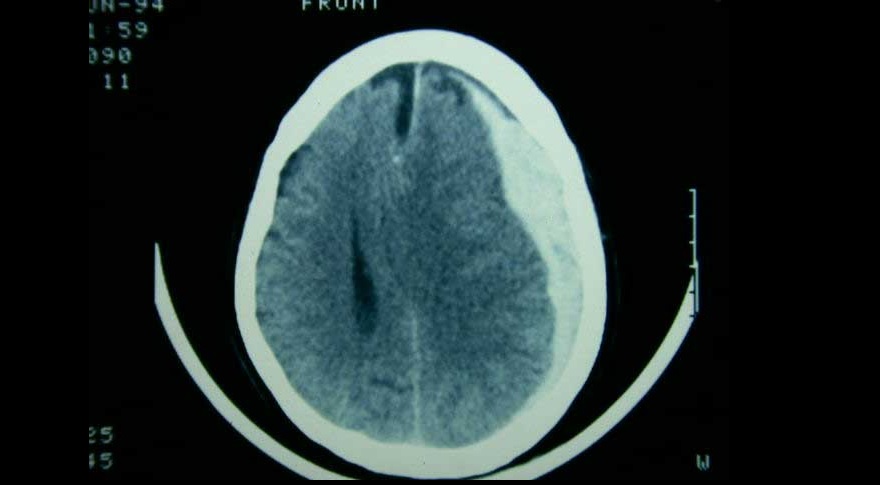

Tres ensayos clínicos exploran la utilidad de la embolización de esta arteria en el manejo del hematoma subdural subagudo o crónico, con miras a reducir la tasa de recurrencias y la necesidad de nuevas intervenciones. New England Journal of Medicine, 20 de noviembre de 2024.

El tratamiento de pacientes con hematoma subdural agudo difiere según el centro de tratamiento, debido a la variación en el abordaje preferido. Una estrategia de tratamiento que prefirió un enfoque agresivo de evacuación quirúrgica aguda sobre el tratamiento conservador inicial no se asoció con un mejor resultado funcional. The Lancet Neurology, 5 de mayo de 2022.